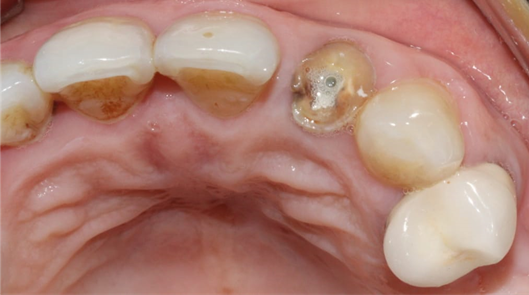

A 54-year-old female patient in good general health visited the outpatient department of the University Hospital Clinic of Odontology in Monastir, Tunisia, for therapeutic management of her left maxillary lateral incisor.Endo-buccal examination (Figure 1) revealed the presence of the 22 root

Figure 1. Occlusal view of the maxilla showing the fractured crown of the 22